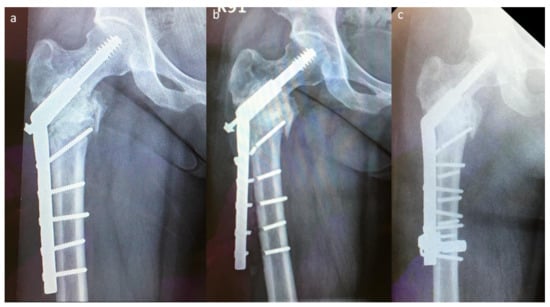

Two implant failures in group A required revision surgery; both patients underwent EPR. Five implant failures in group B required revision surgery, which was performed using the modified SHS technique (Figure 4). The success rate of revision surgery was 100% (5/5) without using a longer SHS side plate, and the implant survival time was >2 years than that observed with the previous SHS constructs.

Figure 4.

An implant failure case in group B: (a) original postoperative X-ray image, (b) first implant failure, and (c) postoperative plain radiograph after revision surgery with modified SHS.